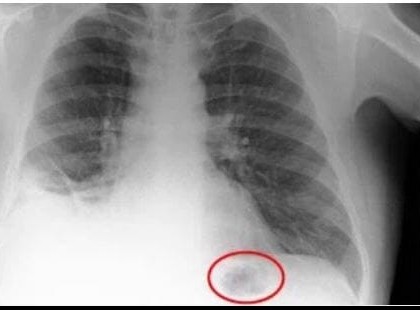

10+1 korai jele annak, hogy rákos vagy

A rákkutatók világszerte, ha sok mindenben nem is, egyben biztosan megegyeznek: a rák gyógyításának legfontosabb...